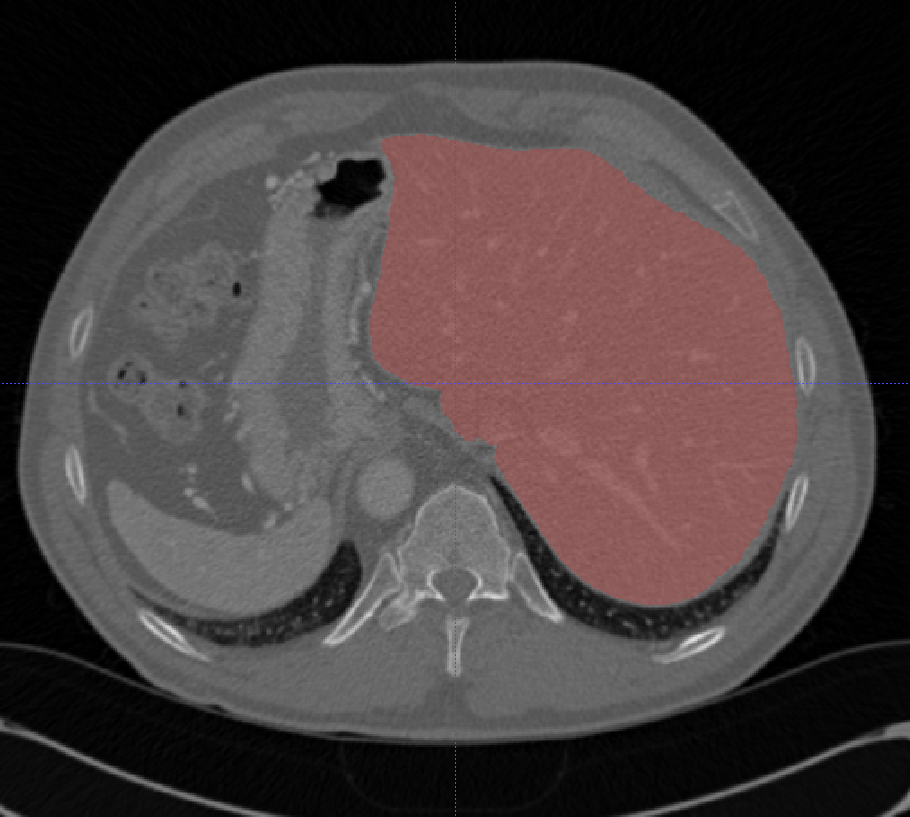

# 肝脏

## LiTS

| 名称 | 标注内容 | 类型 | 模态 | 数量 | 标签格式 | 文件格式 |

| - | - | - | - | - | - | - |

| [LiTS](https://competitions.codalab.org/competitions/17094) | 肝脏/肝脏肿瘤 | 分割 | CT | 130+70 | 0/1标签 | nii |

LiTS数据集包含130组训练数据和70组测试数据,其中70组测试数据是没有标签的。LiTS训练集中包含3DIRCADB中的所有数据,所以如果合并多个数据集不要合并这两个。

分割结果可以在线提交进行评估,[在线提交方法参考](https://github.com/PatrickChrist/LITS-CHALLENGE)。 [在线提交地址](https://competitions.codalab.org/competitions/17094)

数据集论文:[The Liver Tumor Segmentation Benchmark (LiTS)](https://arxiv.org/abs/1901.04056)

相关项目: [基于Paddle的肝脏CT影像分割](https://aistudio.baidu.com/aistudio/projectdetail/250994)

[Aistudio下载](https://aistudio.baidu.com/aistudio/datasetdetail/10273)